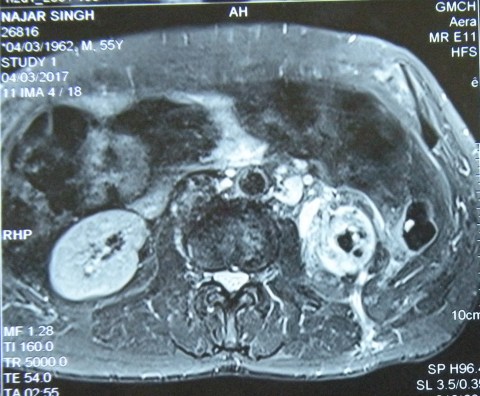

Nephrectomy for a huge renal cell cancer with cystic and solid areas, and with a few stones.